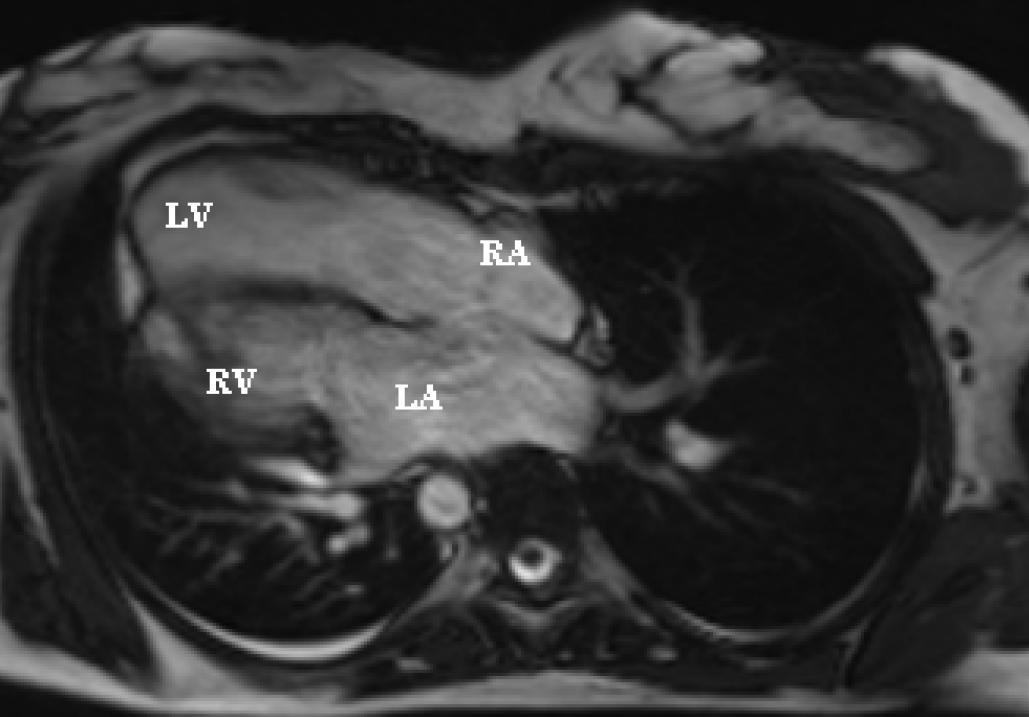

Figure 3